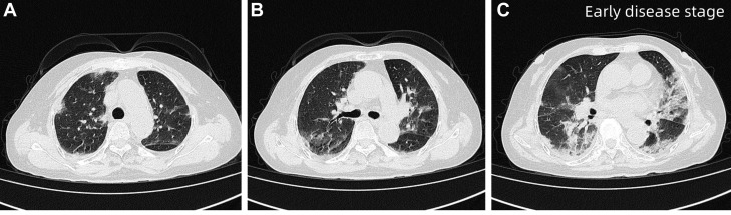

入院时行高分辨率CT(HRCT),显示双肺弥漫性斑片状致密影,边缘模糊,以双下肺为主,局部可见空气支气管征,提示急性弥漫性肺实质受累。

图1 患者入院时HRCT,双肺弥漫性斑片状致密影,边缘模糊,双肺下叶为主要受累区域,局部可见空气支气管征